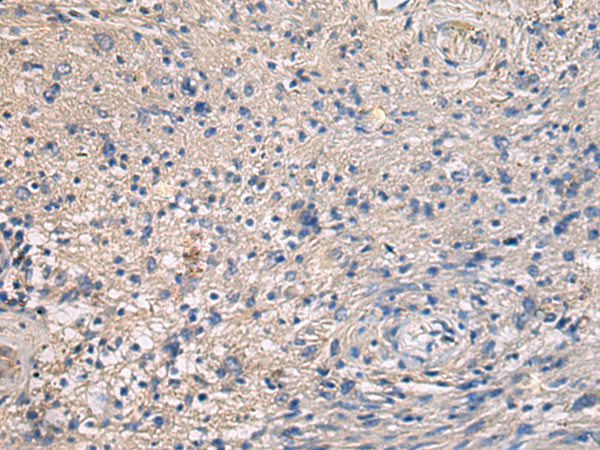

分类: 科研抗体货号: P10423别名: SAV; WW45; WWP4应用: WB,IHC反应种属: Human, Mouse, Rat